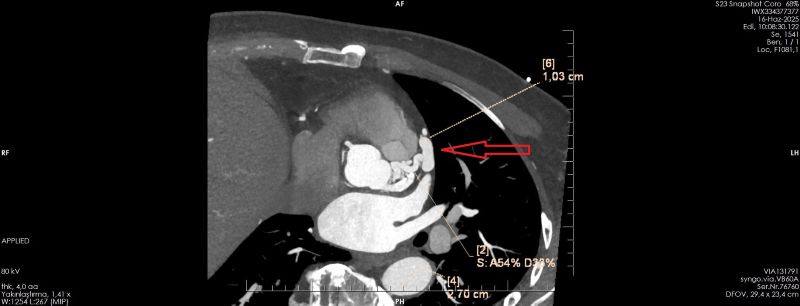

OLGU:

Koroner arterin pulmoner artere füstülizasyonu ile Koroner BT Anjiyografi ile demosterize edilmiş olgu örneğidir.